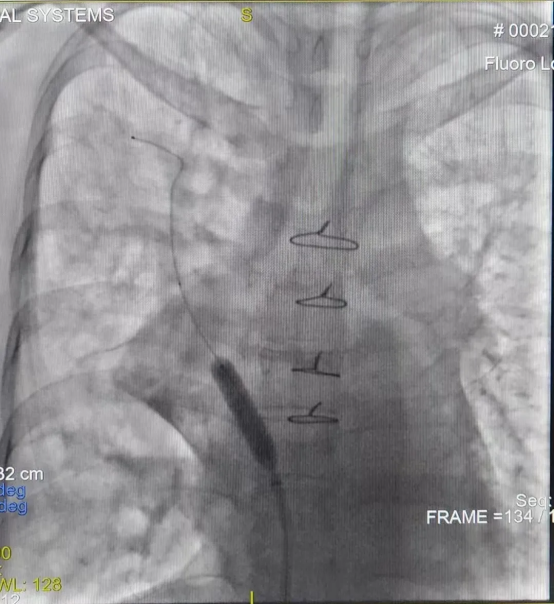

由于该手术难度极高(CMI值达17.8),心内一科与肺血管病与介入医学科联合为其制定周密手术方案。术前肺动静脉增强CT提示左肺动脉狭窄、左上、左下肺静脉闭塞,右上肺静脉狭窄。术中,心内一科尚粉青主任与孙杨医生行右心导管检查,明确其属于“毛细血管前肺动脉高压”。李积安主任、王鹏军副主任医师行经肺动脉间接肺静脉造影,再次证实左上、左下肺静脉闭塞,右上肺静脉狭窄。成功行房间隔穿刺,左肺肺静脉造影发现左上肺静脉完全闭塞,反复导丝尝试后成功开通了闭塞的肺静脉并行球囊扩张及支架植入,后再次行右肺静脉扩张,造影证实肺静脉回流正常,术后患者病情平稳,胸腔积液迅速吸收,症状明显改善,3天后胸腔积液完全消失。9月2日开学之际,李女士康复出院,终于能够回家照顾孩子,重归正常生活。

右上肺静脉球囊扩张